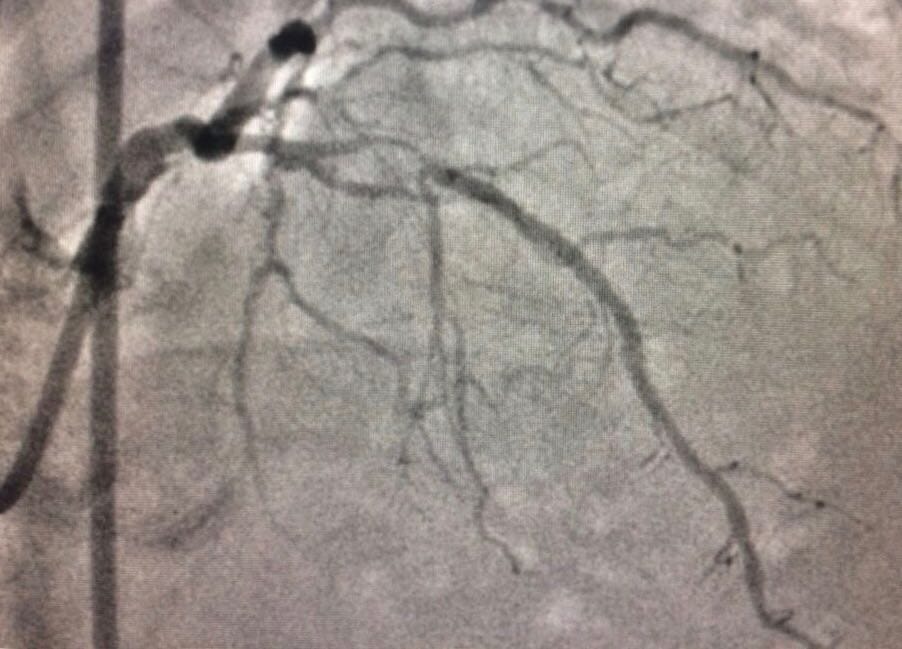

OCT is done in addition to a normal angiography among patients who have blockages and are in need of angioplasty. Normal angiography is done by injecting a radio dye inside the arteries to detect a plaque or blockages, while angioplasty refers to inserting stents that free these arteries from obstruction. OCT, on the other hand, uses infra-red light-based technology.

“The major drawback of angiography was its two-dimensional representation of a three-dimensional object. It often missed the important details about the lesion, the plaque which causes the heart-attack. Sometimes, angiography done on a person who had already had a heart attack showed a clear artery. One couldn’t know the reason for why the heart attack occurred,” Chandra told ThePrint.

The procedure, called OCT, is done in addition to a normal angiography, and produces a three-dimensional image from inside the heart.